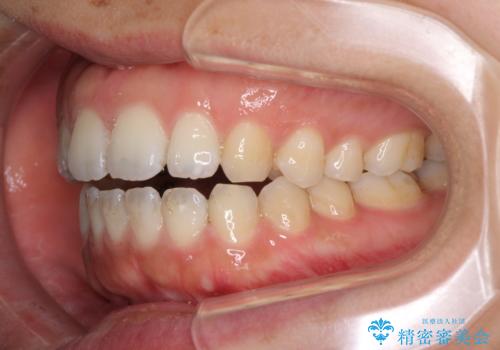

全く目立たないワイヤー矯正 上下リンガル矯正

- 上下の前歯のでこぼこを気にして来院された患者様です。

結婚式が近いこともあり、全く目立たない裏側矯正により口元を整えることとしました。

下顎が左側にずれているため、裏側矯正ということもあり咬み合わせを整えるのに時間がかかってしまいました。